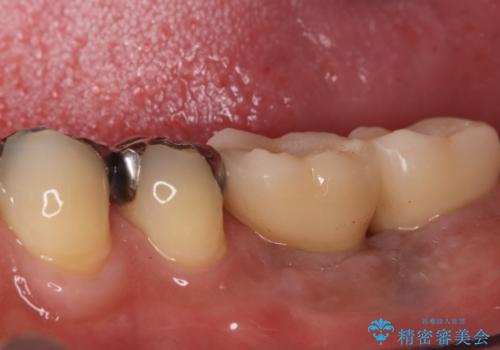

小臼歯のインプラント

- 小臼歯が先天性欠損していたため、インプラントにて補綴しています。